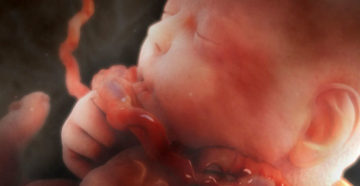

32 неделя беременности: рост, вес, развитие плода, УЗИ 32 акушерская неделя — является 30 неделей…

32 неделя беременности — развитие и расположение плода, ощущения. Фото и видео Из хорошего: была…